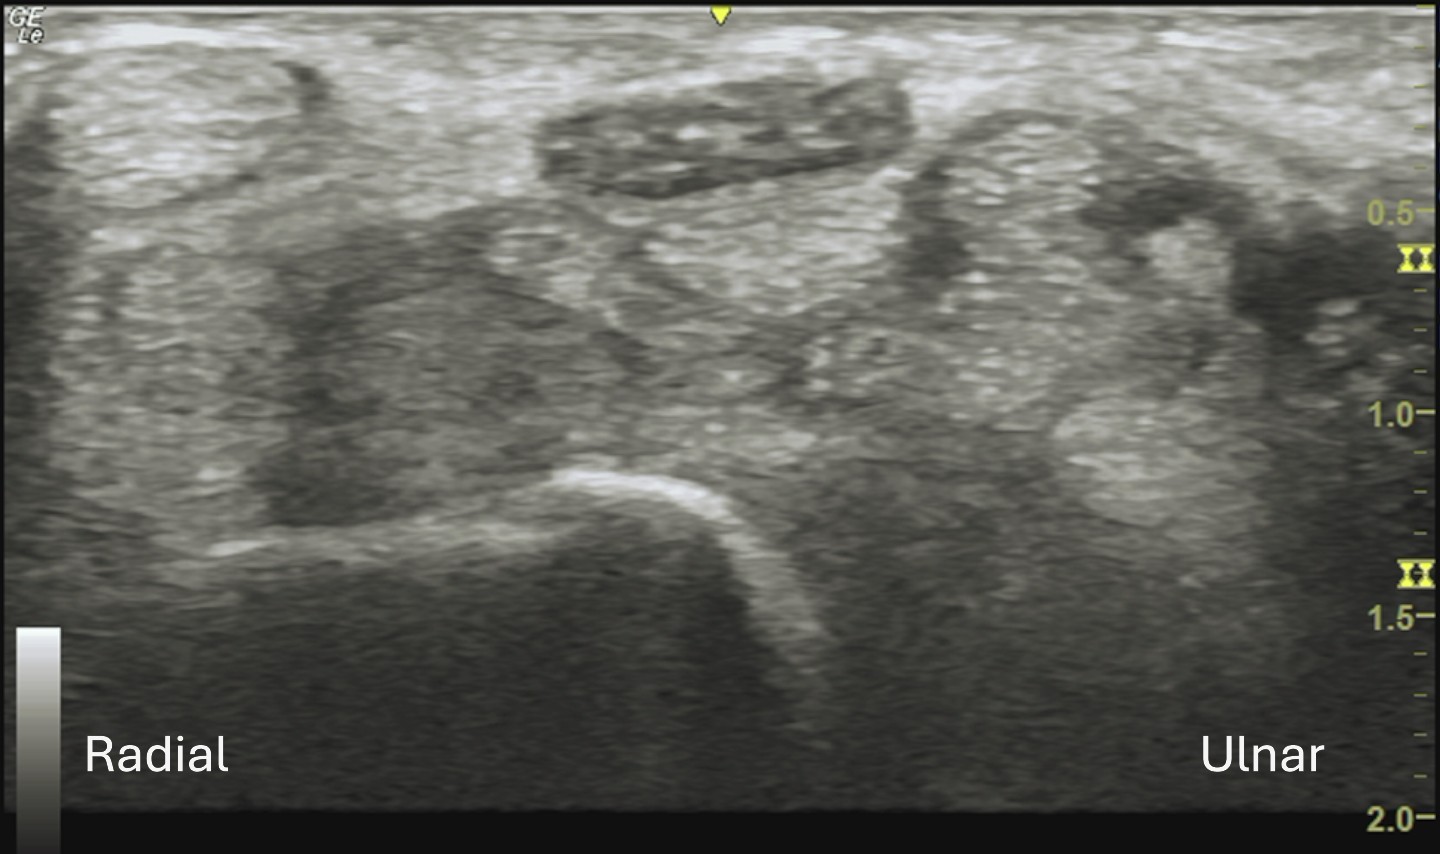

Labeled short axis view of the proximal carpal tunnel with an enlarged median nerve at the carpal tunnel inlet with cross-sectional area (CSA) measuring 25 mm². Normal CSA is <10 mm², borderline is 10-12 mm², abnormal is >12 mm².

Unlabeled short axis view of the proximal carpal tunnel.